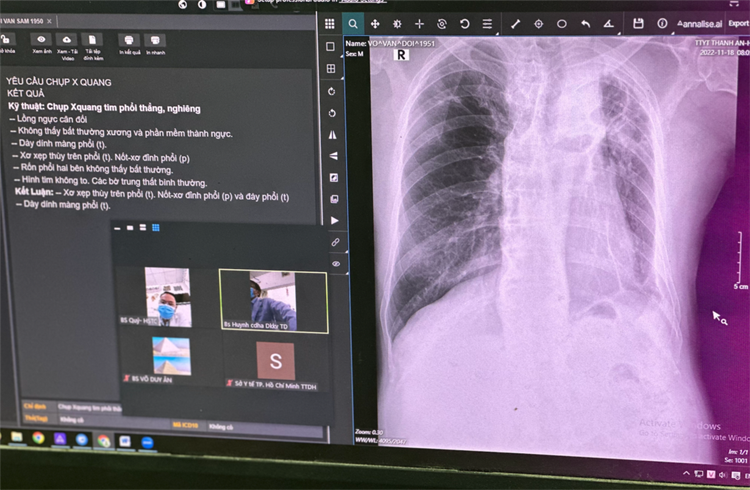

Khi có phim chụp, BS Tỷ khởi động hệ thống trí tuệ nhân tạo (AI) tích hợp trên máy X-quang để đọc phim. Sau ít phút, máy cho ra kết quả bệnh nhân bị xẹp phân thùy phổi P, dày màng phổi và tràn dịch màng phổi T. Với kết quả này, BS Tỷ trao đổi chi tiết hơn với các bác sĩ bệnh viện tuyến trên để lập phác đồ điều trị cho bệnh nhân ngay tại cơ sở.

| Bác sĩ trẻ sử dụng máy X-quang tích hợp AI tại Trạm y tế xã đảo Thanh An |